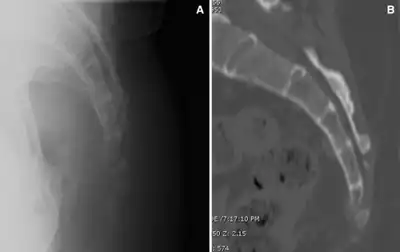

A number of different conditions can cause pain in the general area of the coccyx, but not all involve the coccyx and the muscles attached to it. The first task of diagnosis is to determine whether the pain is related to the coccyx. Physical rectal examination, high resolution x-rays and MRI scans can rule out various causes unrelated to the coccyx, such as Tarlov cysts and pain referred from higher up the spine. Note that, contrary to most anatomical textbooks, most coccyxes consist of several segments: 'fractured coccyx' is often diagnosed when the coccyx is in fact normal or just dislocated at an intercoccygeal joint.[6][7]

If the anesthetic test proves positive, then a dynamic (sit/stand) x-ray or MRI scan may show whether the coccyx dislocates when the patient sits.[9]